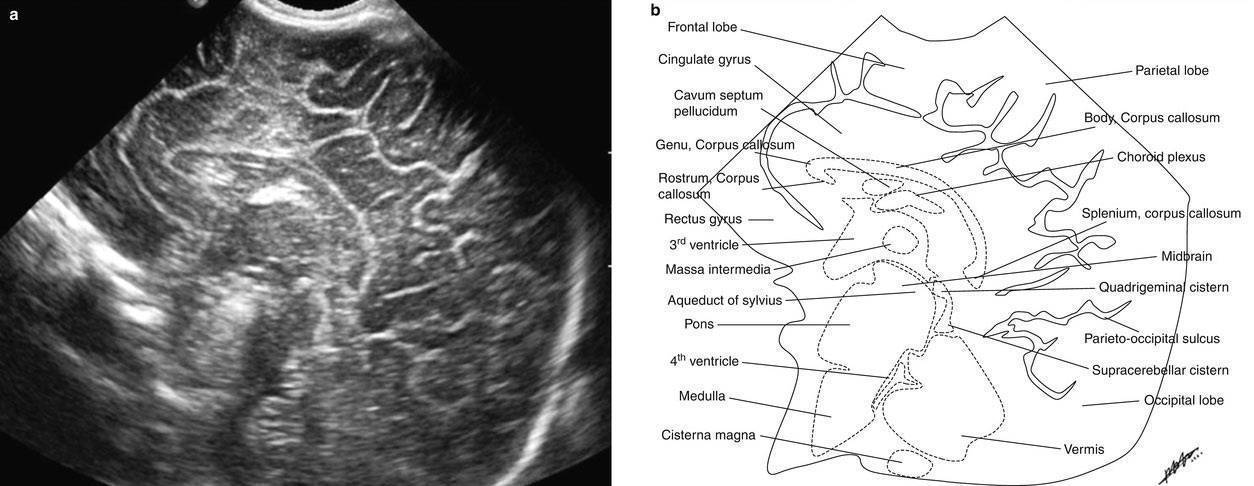

Рисунки: снимки и расположение структур мозга

Борозды и извилины коры мозга отражают степень его зрелости. Извилины полушарий активно дифференцируются с 28 недели беременности и становятся видны при УЗИ спустя 2-6 недель после того, как сформируются в анатомические структуры. После рождения ребенка локализация и количество борозд и извилин в норме соответствуют строению мозга взрослого человека.